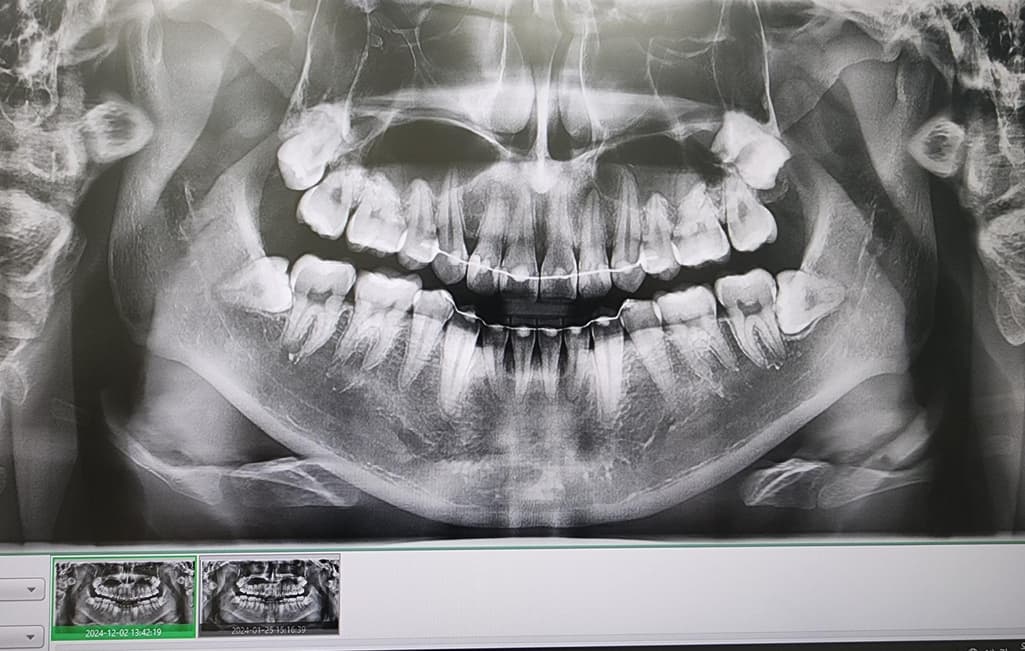

사진상 앞니 오른쪽 뿌리끝에 작은 염증이 있다고 합니다

사진은 24년1월 24년 12월 25년 5월 순입니다

• 1번 째 사진

사진상으로는 염증이 명백히 보이지만 증상이 없다면 일단 지켜보는 것도 괜찮을 것 같습니다.

엑스레이 상으로는 크게 염증이 커지거나 그렇진 않은거 같습니다. 증상이 없다면 정기적으로 치과를 다니시면서 관리를 받으시면될것같습니다.

파노라마 사진상으로 측은단 부위에 병소가 보이고 있습니다. 정확한 확인을 위해서는 CT 촬영을 해보는 것이 좋을 것으로 생각되며 치근단 질환이 생겼다는 것은 근관 내가 이미 감염이 되었다는 것이기 때문에 치근단 질환이 있다면 신경 치료를 해줘야 합니다. 그렇지 않다면 주변에 있는 치조골이 손상되어 나중에는 치아를 손실 할 수도 있습니다.